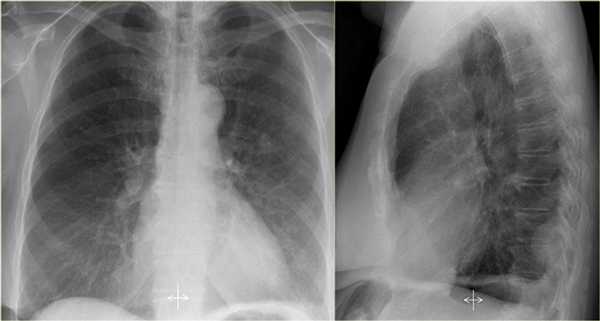

Ателектаз нижней доли левого легкого

На рентгенограмме визуализируются изменения трехгранной формы высокой плотности, расположенные позади тени сердца, что хорошо выявляется на боковом снимке. На боковом снимке при оценке контура диафрагмы спереди назад определяется все менее четко. Исходя из названия раздела напрашивается диагноз — ателектаз нижней доли левого легкого. В норме прозрачность легкого внизу выше, а в нашем случае наоборот (синяя стрелка).